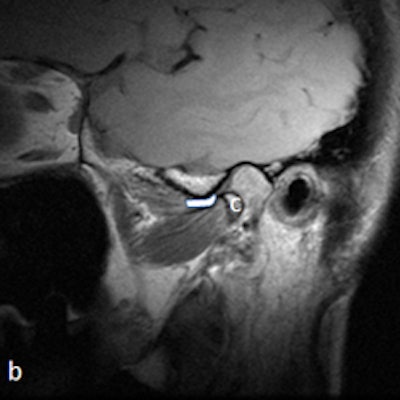

Dr. Friedman prefers that patients be supine on a stretcher with the jaw tilted away from the side to be examined. Then the person performing the ultrasound palpates the joint while the patient opens and closes her mouth. Gel is then placed on the joint, and the probe is placed at various positions around the joint. The images are examined to determine whether there is anterior displacement of the disk while the joint is the closed-mouth position.

"If the ultrasound is abnormal, the patient should be referred for an MRI, and any patient scheduled for surgery also must have an MRI," he said. "The main challenge is learning to detect what is normal on ultrasound. We also acknowledge that abnormal anteromedial and medially displaced disks may be missed or misinterpreted with ultrasound."